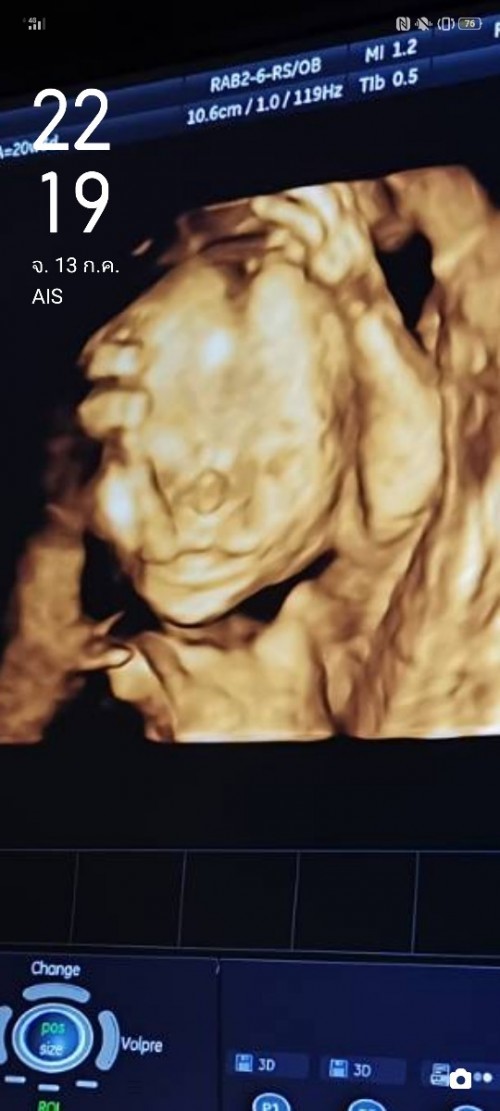

āđāļāđāļāļāļđ āļŦāļĨāļāļĨāļđāļ #āļāļāļāļđāđāļāļāļēāļ§āļāđāļāļĩāļĄāļāļļāļĨāļēāļŦāļāđāļāļĒāļāđāļ° ðĨ°ð§ļ